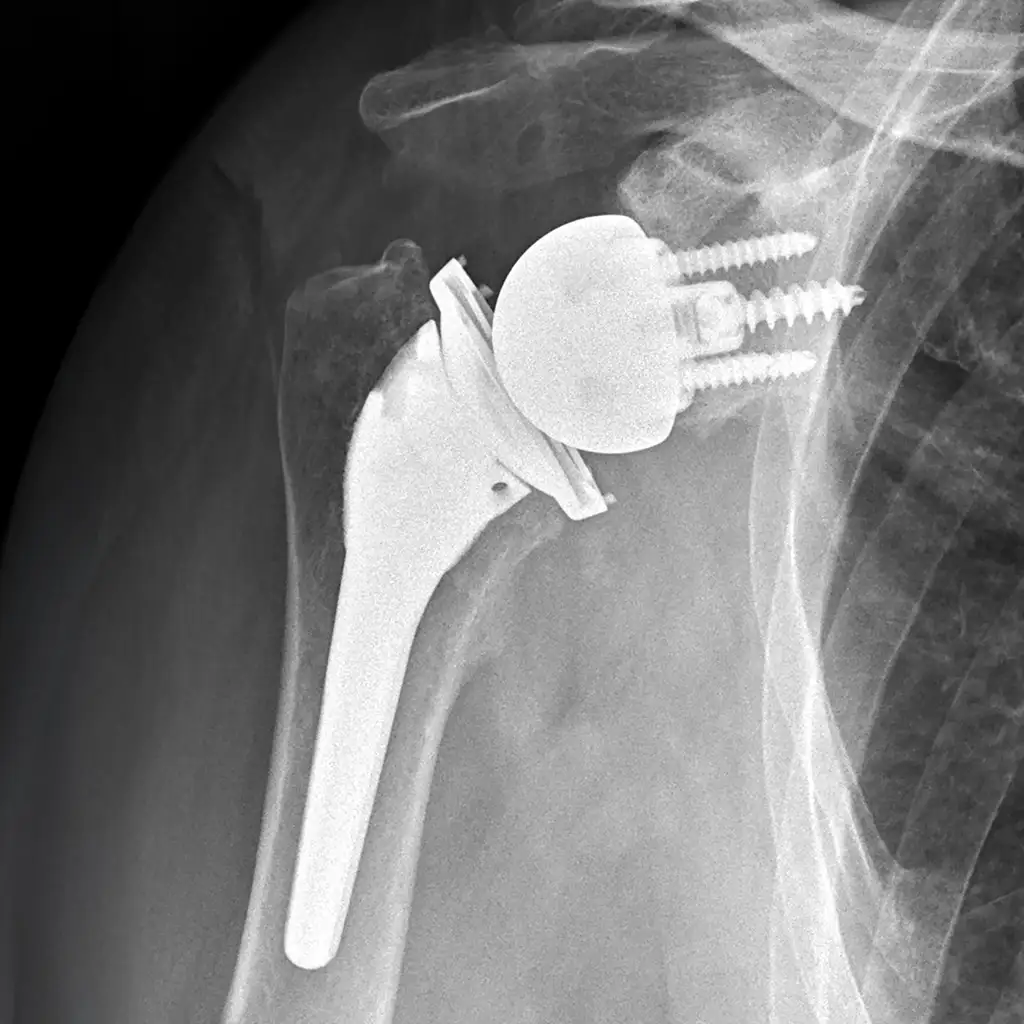

Reverse Shoulder Replacement

A reverse shoulder replacement can help relieve severe shoulder pain and improve arm function when the rotator cuff can’t be repaired. It uses a specialized implant design that allows other muscles to restore more comfortable, reliable movement.